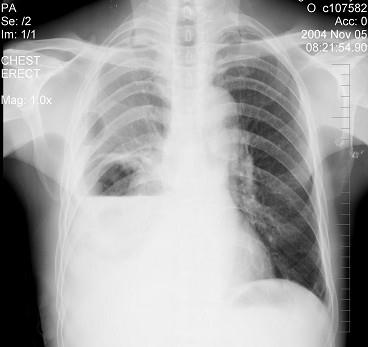

问题 男性患者,64岁,咳嗽高热多日,无痰中带血,X线检查如图,最合理的诊断是 ( )

选项 A.右侧胸腔积液 B.右侧胸腔积液并肺脓肿 C.右肺炎 D.右肺不张 E.右支气管扩张

答案 B